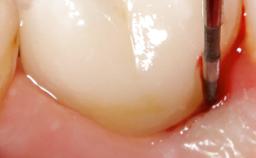

A 79-year-old female patient was referred to the Department of Periodontology of the University of Bern, Switzerland by her private dentist in May 2019. She had been rehabilitated in May 2005 with two tissue-level implants (Institut Straumann AG, Basel Switzerland) at sites 13 and 15, supporting a three-unit cemented fixed dental prosthesis (FDP). The metal-ceramic FDP had been cemented permanently with a glass-ionomer cement (Ketac Cem; 3M ESPE, Seefeld, Germany). Implant 13 had been diagnosed with peri-implant mucositis by the referring dentist in the course of regular supportive therapy. The patient was in good general health, did not smoke, and exhibited good self-performed plaque control.